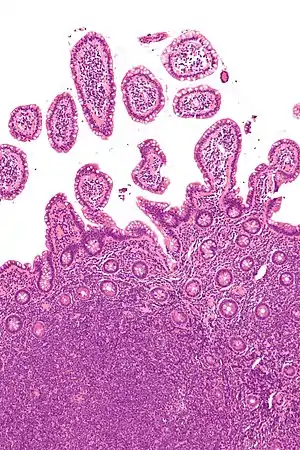

Linfoma de células do manto (LCM) é um linfoma não-Hodgkin originado de linfócitos B do centro pré-germinal dos folículos linfáticos primários ou na região do manto de folículos linfáticos secundários. Representa 2-10% de todos os linfomas não-Hodgkin. É quatro vezes mais comum entre homens. A idade média no momento do diagnóstico é de 60 anos.[1]